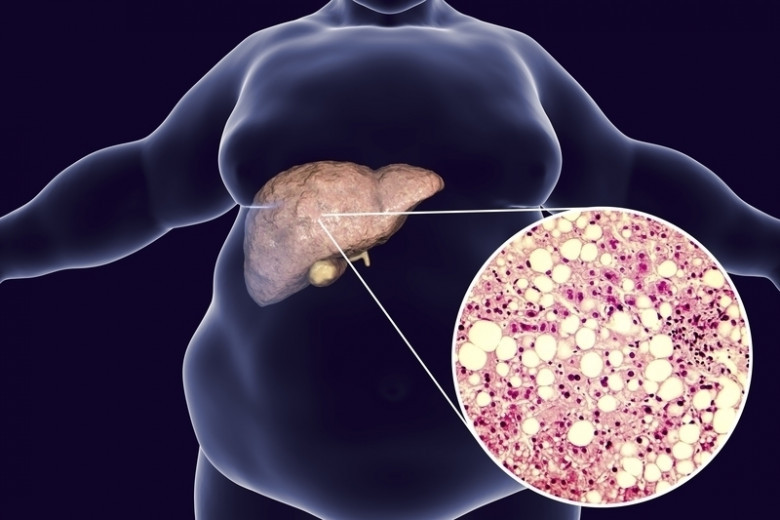

Fatty liver is in voorgaand onderzoek meermaals geassocieerd met obesitas, type 2 diabetes, hoge bloeddruk en lipide (vet) verstoringen. Als er niks aan gedaan wordt, kan fatty liver leiden tot cirrose, waarin leverweefsel onomkeerbaar omgezet wordt in littekenweefsel. Met levensbedreigende consequenties. De oorzaak van fatty liver is voornamelijk een ongezonde levensstijl – dus te veel suiker en een gebrek aan beweging – maar heeft ook een genetische component.

Analyse van de weefsels lieten vervolgens zin dat een dieet op basis van calorierestrictie en een hoge eiwitinname effectiever was dan een dieet op basis van calorierestrictie en een lage eiwitinname. Effectiever in de zin dat de hoeveelheid lever vet afnam met 40 procent in de hoge-eiwitgroep. In de lage-eiwitgroep bleef de hoeveelheid lever vet daarentegen gelijk. De deelnemers aan de studie verloren beiden hetzelfde gewicht door de calorierestrictie; beide groepen gemiddeld 5 kilogram. Andreas Pfeiffer, hoofd van de onderzoeksgroep zegt hierover: “Als de resultaten van grotere studies ook deze kant op blijven wijzen, zullen de aanbevelingen voor een hogere eiwitinname samen met een gezond dieet met minder vet onderdeel worden van een effectieve therapie voor fatty liver.”